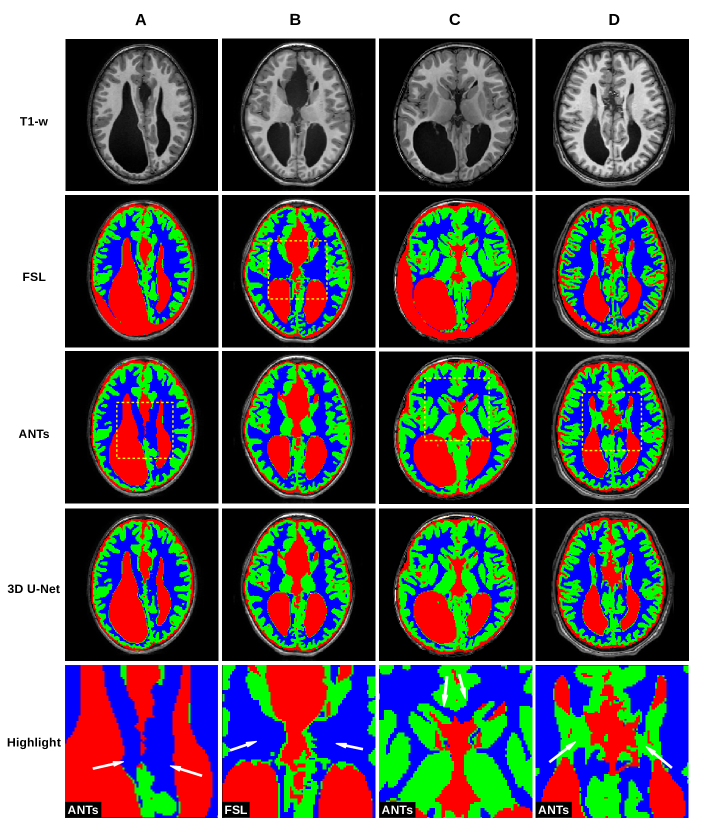

Agenesis of Corpus Callosum. 12 patients with agenesis of corpus callosum (ACC) (average age 5.8 (SD=5.2)). Callosal agenesis is characterized by colpocephaly, parallel ventricles, presence of Probst bundles and upward extension of third ventricle. See some cases in Figure 1.

In Figure 1, we show a paradigmatic set of axial slices segmented by FSL, ANTs and the 3D U-Net, from patients with ACC, i.e. from 4 of the 12 subjects described in Section 2.2. Similarly, in Figure 2, we report paradigmatic axial slices segmented by those methods, from 4 of the subjects with complex cerebral distortions. For the segmentations of all methods, we re-labeled as CSF all the voxels inside the brain mask of each patient that were incorrectly segmented as background. In both figures in the last row, for each subject, we highlight a detail of the slice for one of the segmentation methods (indicated with a dashed square, above in the same column). Such details are discussed in Section 5.

Figure 1 shows that FSL fails to segment GM and WM in cases of moderate and severe ventricular dilatation with thinning of the WM (case A, C and less evident in D). In one case (B) FSL also misses identifying the thalami as (deep) GM. ANTs performs better in identifying (deep) GM and the cortex at the convexity. However, case A and C show that it may fail in differentiate between GM and subcortical WM on the mesial surface of the hemispheres. This may be related to the prior used by that pipeline, which is based on the anatomy of normal subjects and not designed to recognize spatial reorganization of the cortex, especially in the midline, like in ACC cases. A similar error is in case C where a cortical component close to the head of the caudate is misclassified as WM. Finally in D, Probst bundles, which are abnormal WM tracts running parallel to the medial ventricular wall, are labelled as GM. In contrast, the 3D U-Net performs well in segmenting ACC. The most relevant error in these cases is at the interface between ventricles and WM: the 3D U-Net wrongly identifies a very thin layer of GM along the inner ventricular surface. This is probably related to partial volume effects.